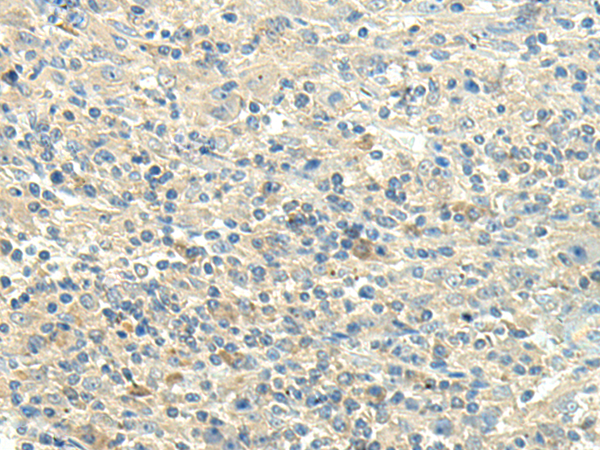

分类: 科研抗体货号: P10813别名: SAG; GP340; SALSA; muclin应用: IHC反应种属: Human, Mouse, Rat